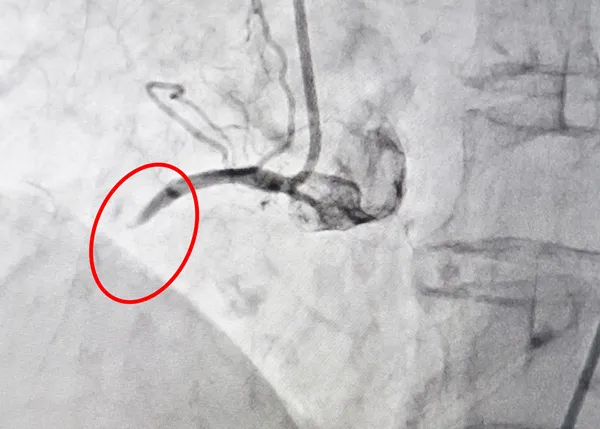

Kết quả xác định cụ S. bị nhồi máu cơ tim cấp. Mặc dù đã được điều trị bằng thuốc, nhưng tình trạng bệnh nhân đáp ứng kém: vẫn còn đau ngực, khó thở và men tim tiếp tục tăng. Vì thế, bệnh nhân cần phải được can thiệp cấp cứu. Kết quả chụp DSA cho thấy, nhánh động mạch vành bên trái của bệnh nhân hẹp khít 90% - 95%, nhánh động mạch vành bên phải bị tắc nghẽn hoàn toàn.

Các bác sĩ Trung tâm Can thiệp tim mạch BV Xuyên Á nhanh chóng tiến hành can thiệp mở thông và đặt stent động mạch vành bên phải. Ca can thiệp diễn ra thành công. Sau can thiệp, động mạch vành phải của bệnh nhân đã khôi phục dòng chảy bình thường. Hiện tại, tình trạng bệnh nhân đã ổn định.